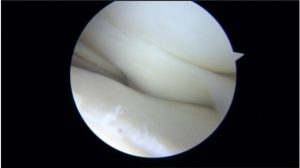

The diagnosis of hypermobile lateral meniscus is a clinical diagnosis only confirmed during the arthroscopy.